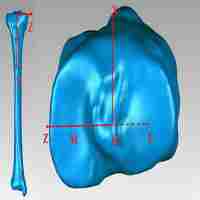

| Abstract | Knowledge of anterior–posterior (A-P) tibial contact locations provides an objective assessment of the relative motion of the tibia on the femur following total knee arthroplasty (TKA), which can be used to compare the effects of different components, surgical techniques, and alignment goals on knee function in vivo. Both the lowest point method and the penetration method have been used to calculate A-P tibial contact locations using three-dimensional (3D) model to two-dimensional (2D) image registration. The primary objective of this study was to quantify errors in calculating the A-P tibial contact location using the lowest point and penetration methods because the errors in calculating the A-P tibial contact locations using these two methods are unknown. The A-P tibial contact locations were calculated with the two methods and simultaneously measured with a tibial force sensor in ten fresh-frozen cadaveric knee specimens with a TKA. Single-plane radiographs of the knee specimens were acquired at 0 deg, 30 deg, 60 deg, and 90 deg of flexion in neutrally, internally, and externally rotated orientations. While the radiographs were exposed, reference A-P tibial contact locations were simultaneously collected using the tibial force sensor to be compared to the calculated A-P tibial contact locations. The overall root-mean-squared-errors (RMSEs) in the A-P tibial contact location calculated with the lowest point method, the penetration method with penetration, and penetration method without penetration were 5.5 mm, 3.6 mm, and 8.9 mm, respectively. The overall RMSE was lowest for the penetration method with penetration, making it the superior method for calculating A-P tibial contact locations. |